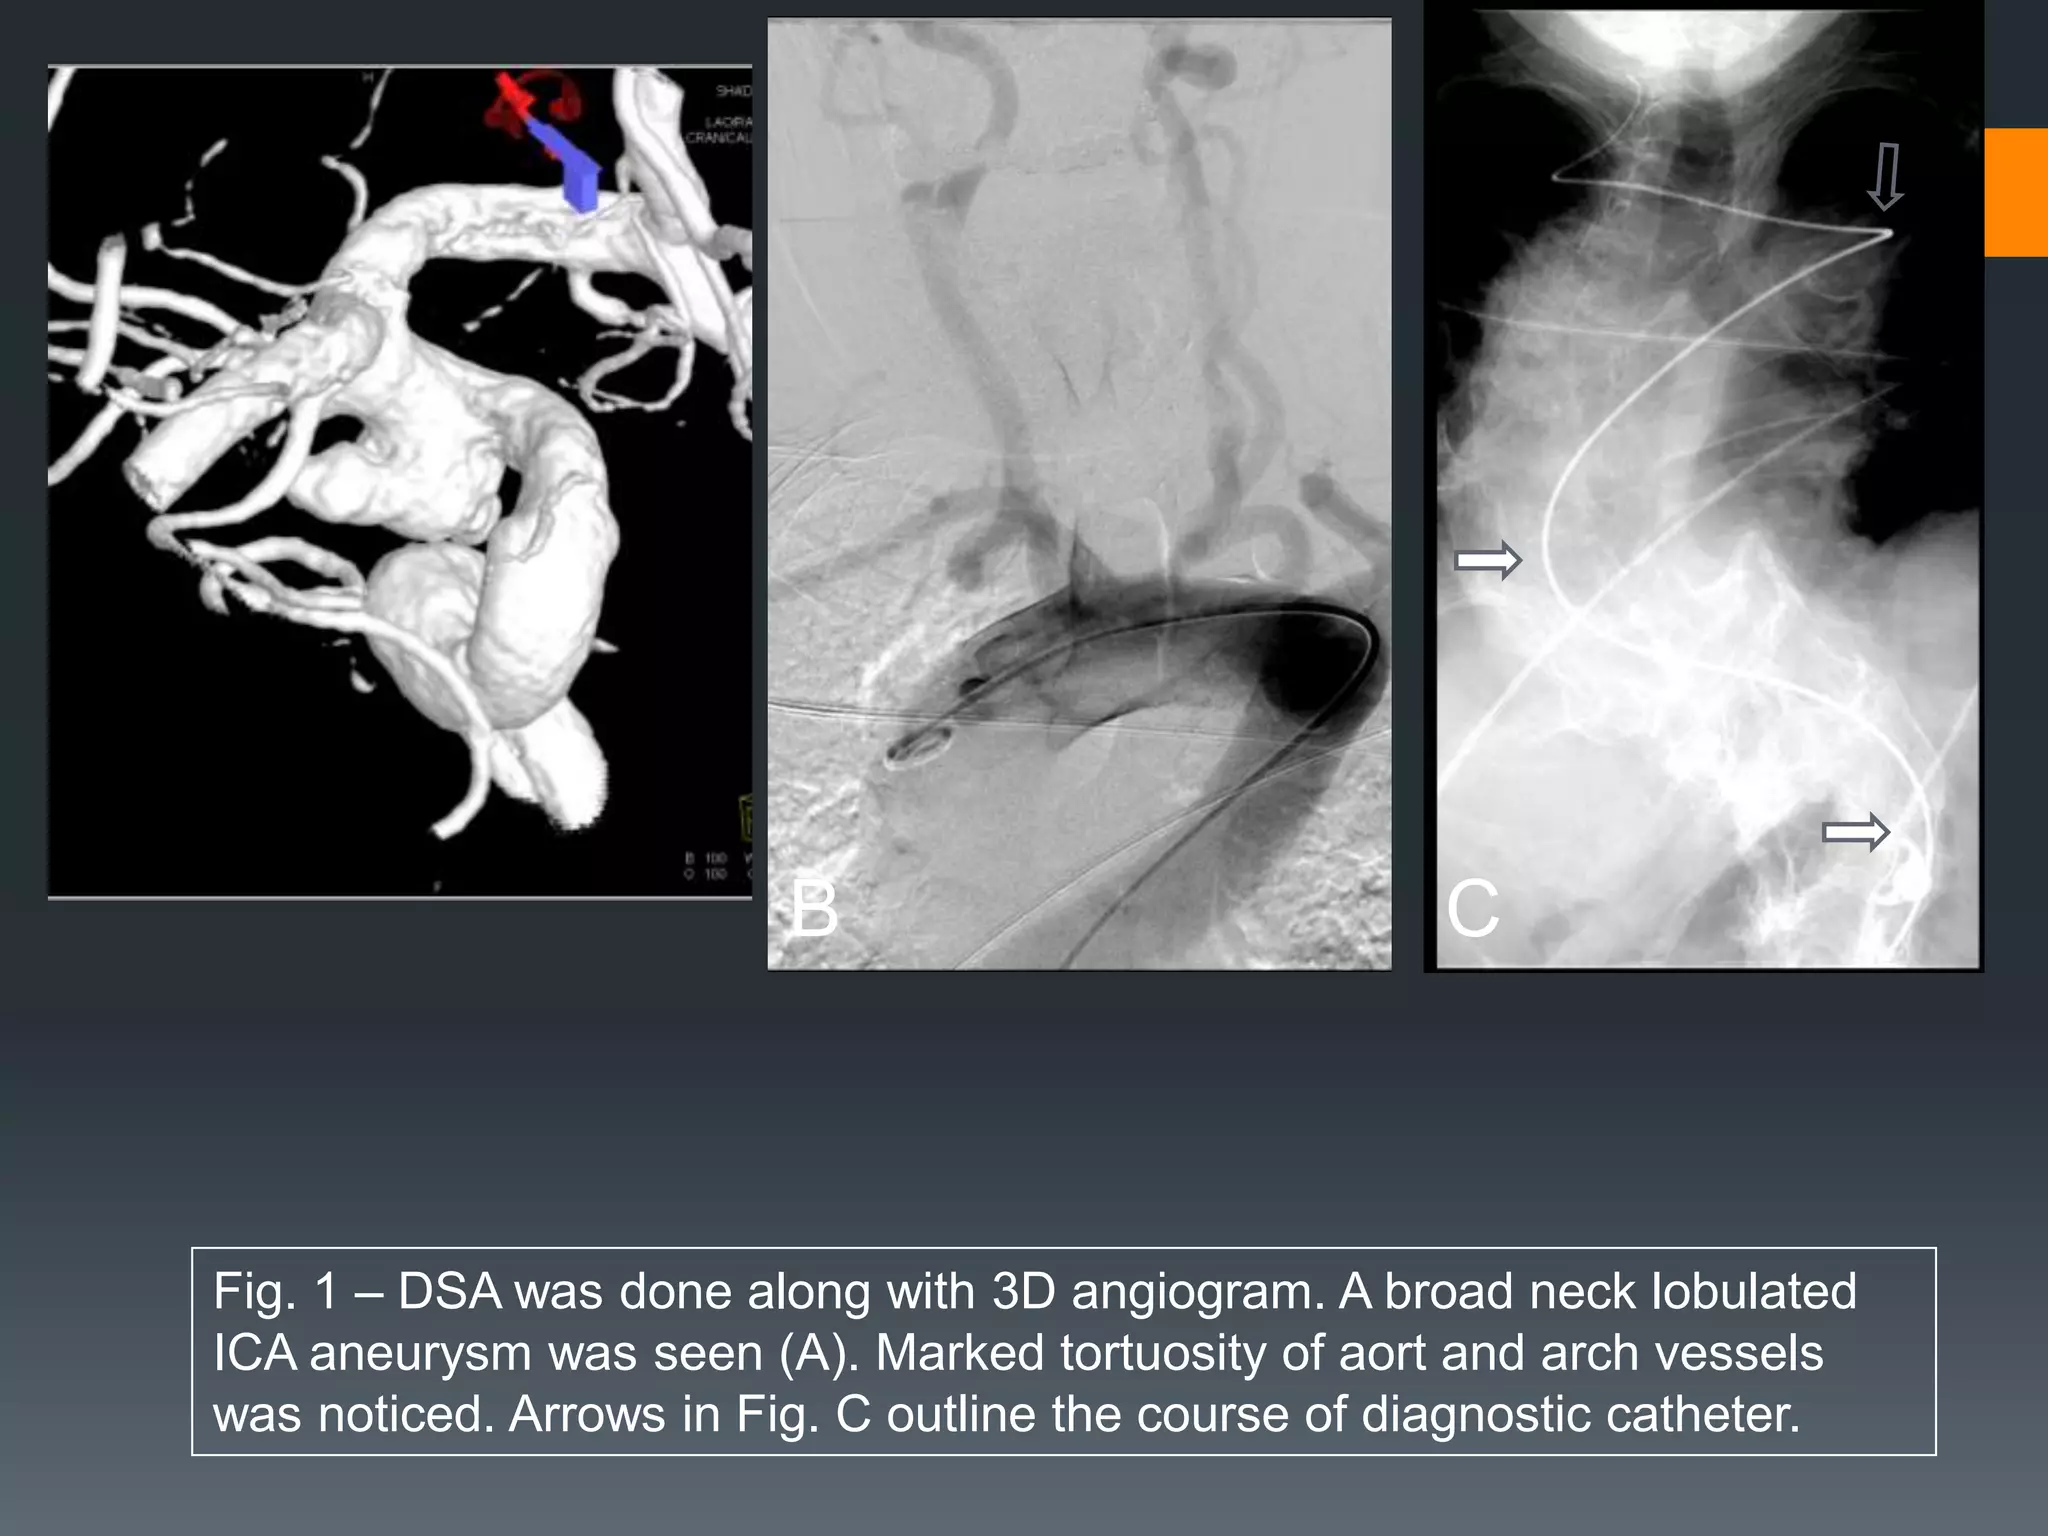

This document discusses tricks and techniques for difficult cannulations during neurointerventional procedures. It outlines strategies for accessing the aortic arch, internal carotid artery (ICA), and areas distal to aneurysms. Long sheaths, distal access catheters, and co-axial techniques are presented as options that have improved cannulation success. Guidance on sheath and catheter selection is provided for different vessel paths. The importance of catheter placement as high as possible in the ICA is emphasized. Reverse curve cannulations are also mentioned. Overall, the document stresses that careful cannulation is critical for procedural success and different strategies may be needed depending on the vessel target.